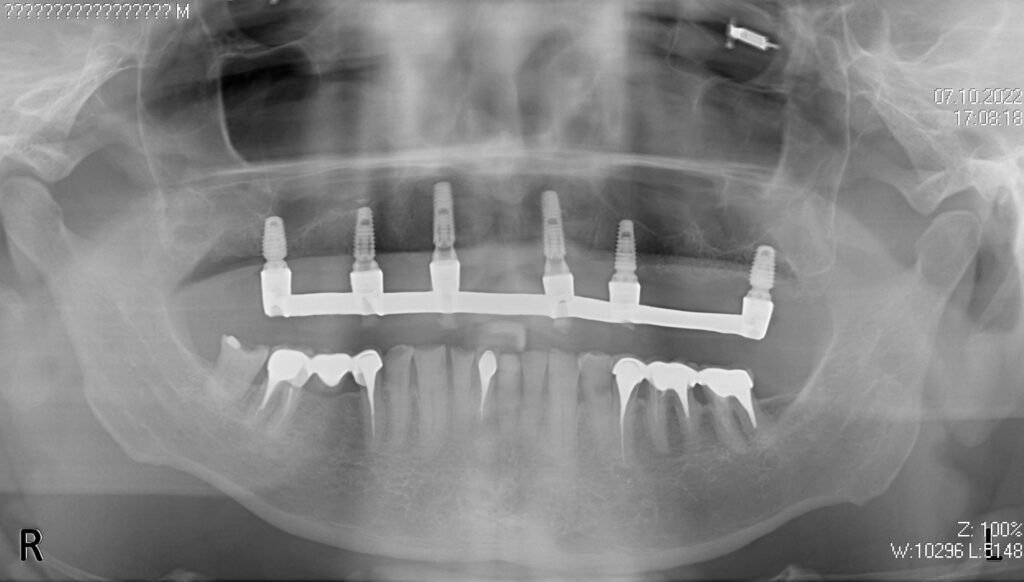

Ситуация до лечения

пациент до имплантации

Что было сделано:

На верхней челюсти были удалены зубы и проведена комплексная имплантация по системе All-on-6,

установлены 6 имплантатов Megagen AnyOne.

Спустя 7 дней на верхней челюсти зафиксирован металлоакриловый протез из 12 зубов.

снимок